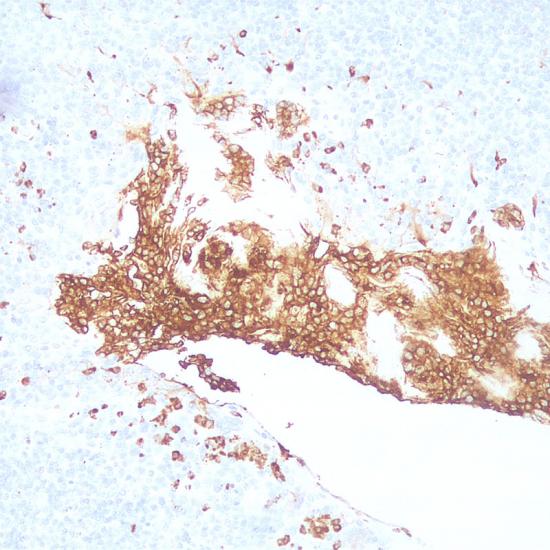

CD11b又稱為CR3或CD18分子。CD11b在骨髓系細(xì)胞中表達(dá),通常用作骨髓系細(xì)胞的一個(gè)標(biāo)記物,如中性粒細(xì)胞、單核細(xì)胞、巨噬細(xì)胞和小膠質(zhì)細(xì)胞。

• 陽(yáng)性部位:

細(xì)胞膜

• 陽(yáng)性對(duì)照:

扁桃體